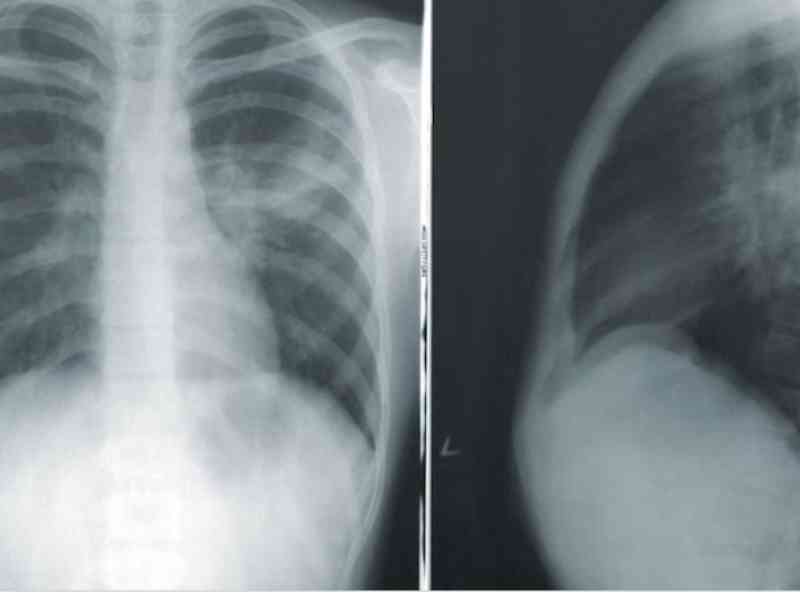

I didn’t treat this patient, but I was on shift when this guy came in with chest pain. His EKG showed tombstone shapes, meaning he was in the middle of a cardiac episode. He told the emergency doctor, “I want a second opinion before going to the cath lab.” This EKG is unmistakable. The interventionalist had to come down to the emergency department to tell him he was having a heart attack.